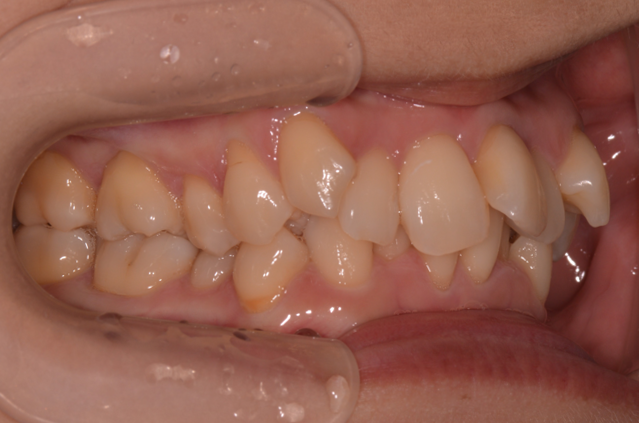

症例1

| 項目 | 詳細 |

|---|---|

| 患者様データ | 30代 女性 |

| 来院時の主訴 | 「上下のガタガタ歯並びと噛み合わせが気になる。」 |

| 矯正法 | 上の歯2本を抜歯しての矯正 |

| 通院期間 | 2年9ヶ月 |

| 治療費 | 総額:1,070,000円(税抜) 【内訳】 精密検査50,000円、メタルワイヤー矯正800,000円、月に1度の調整料5,000円、後戻り防止のリテーナー35,000円×2 |

| リスクと副作用 |

①歯を動かす事による痛みがあります。また、装置に慣れるまでは、口内炎ができやすいです。 ②歯肉が退縮するリスクがあります。装置が全ての歯に付くので、ハミガキが難しくなります。 ③長期的なメインテナンスが必要 |

| ここがこだわりのポイント!☝ |

この患者様の場合、歯並びのガタガタが強かったことや、抜歯したスペースを埋めるのに時間がかりました。ホームケアも大変だったと思いますが、とてもきれいな歯並びに改善することができました。 |